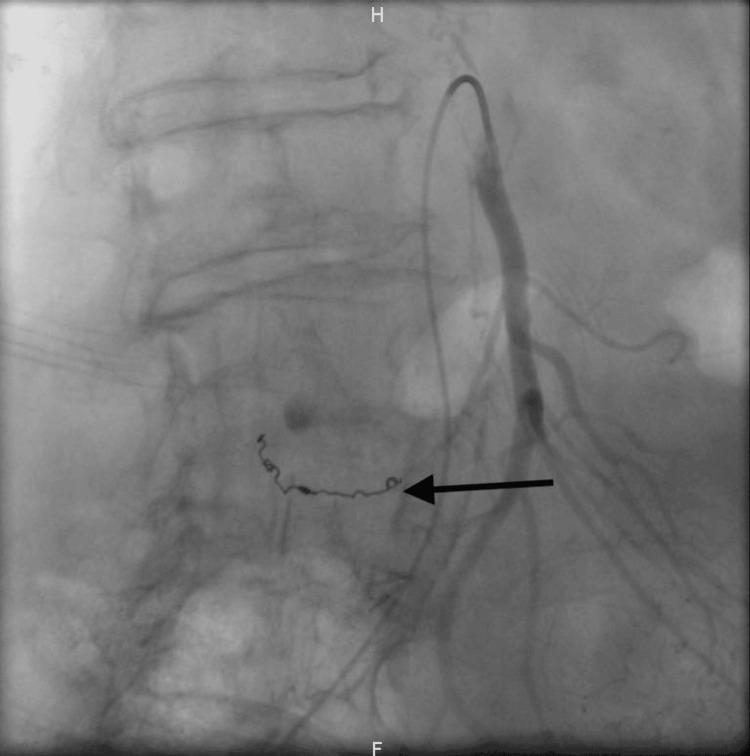

Spontaneous isolated dissection of the superior mesenteric artery (SIDSMA) is a rare condition, particularly when complicated by hemorrhagic shock. This case report describes the discovery of SIDSMA in an 88-year-old woman through CT angiography. The patient initially presented with acute abdominal pain, nausea, and diarrhea, which later progressed to hemorrhagic shock. After fluid resuscitation, the patient underwent successful endovascular treatment.

自发性孤立性肠系膜上动脉夹层(SIDSMA)是一种罕见的病症,尤其是当并发失血性休克时。本病例报告描述了通过CT血管造影在一名88岁女性中发现SIDSMA的情况。患者最初表现为急性腹痛、恶心和腹泻,随后进展为失血性休克。经过液体复苏后,患者接受了成功的血管内治疗。